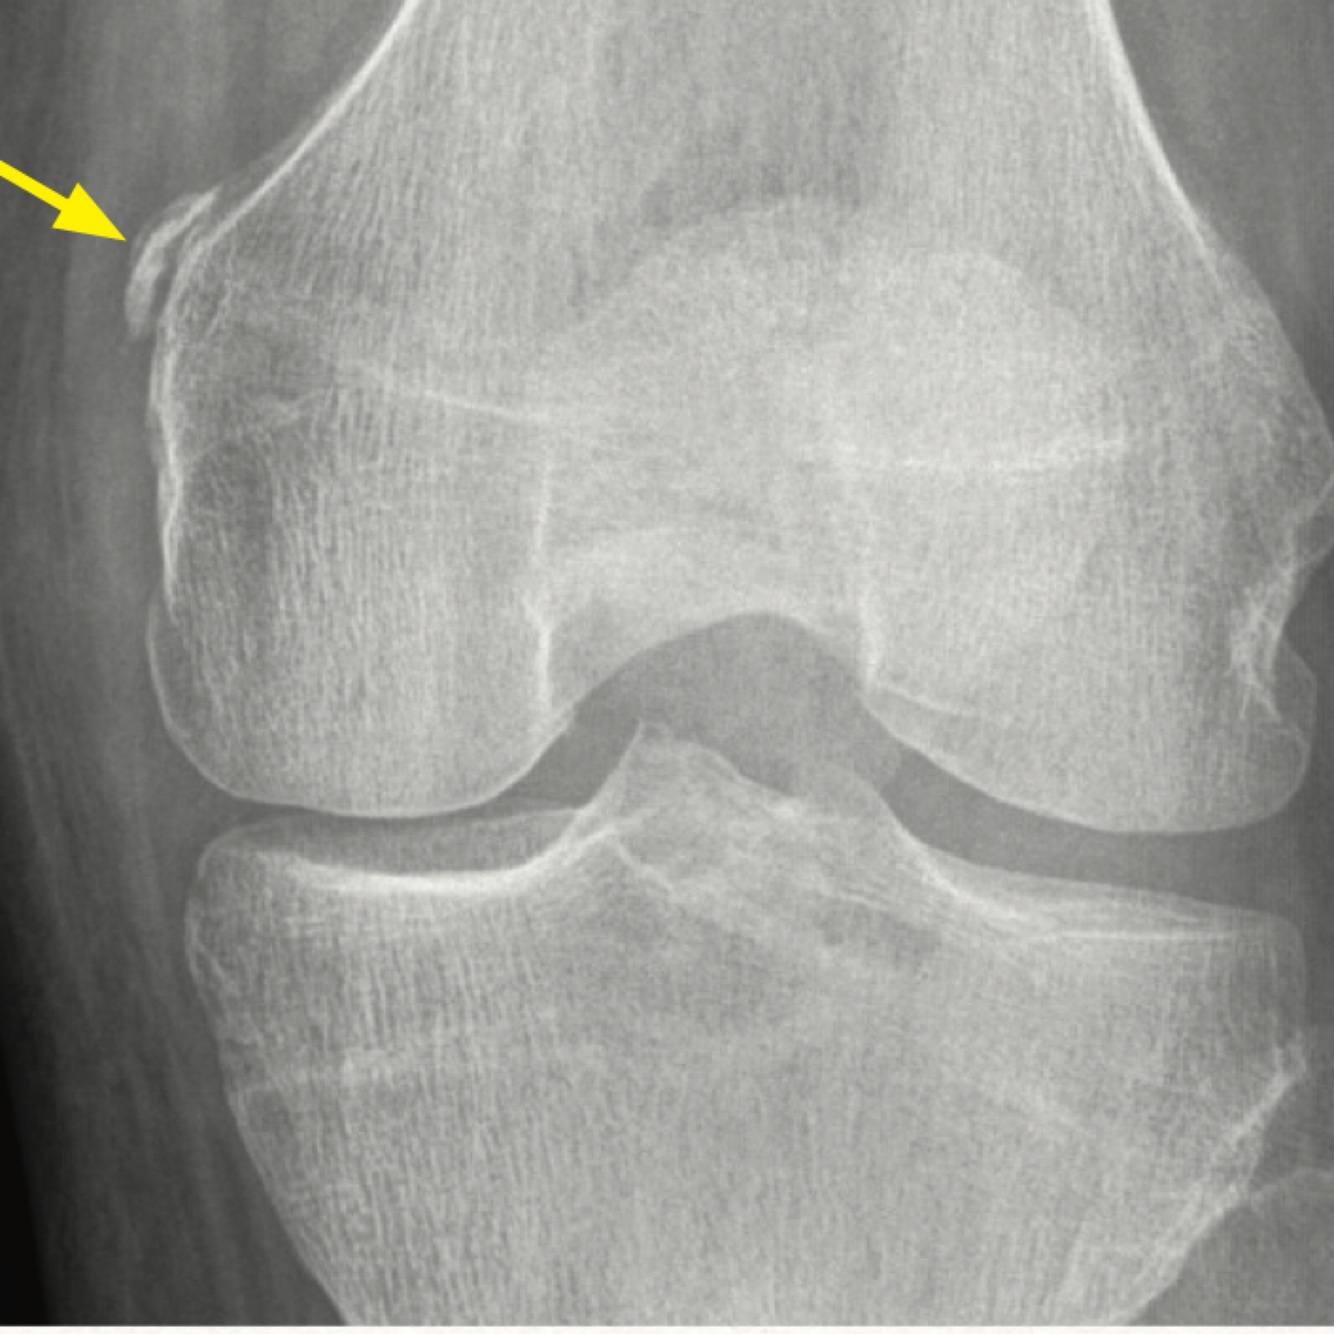

Q

What sign is this image representing and what injury does it indicate

A

Double PCL sign - displaced meniscal fragment flips centrally into the intercondylar notch from bucket handle tear of the medial meniscus